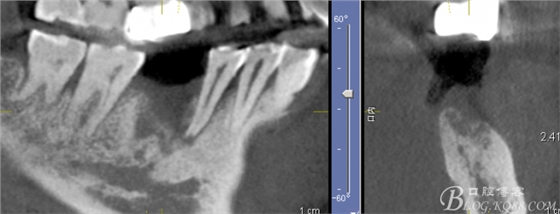

CT可見根管內(nèi)有白色顯影物和根周較大暗影

從根管影像看治療還是不錯的,

懷疑牙根微裂,

所以建議患者手術(shù)探查